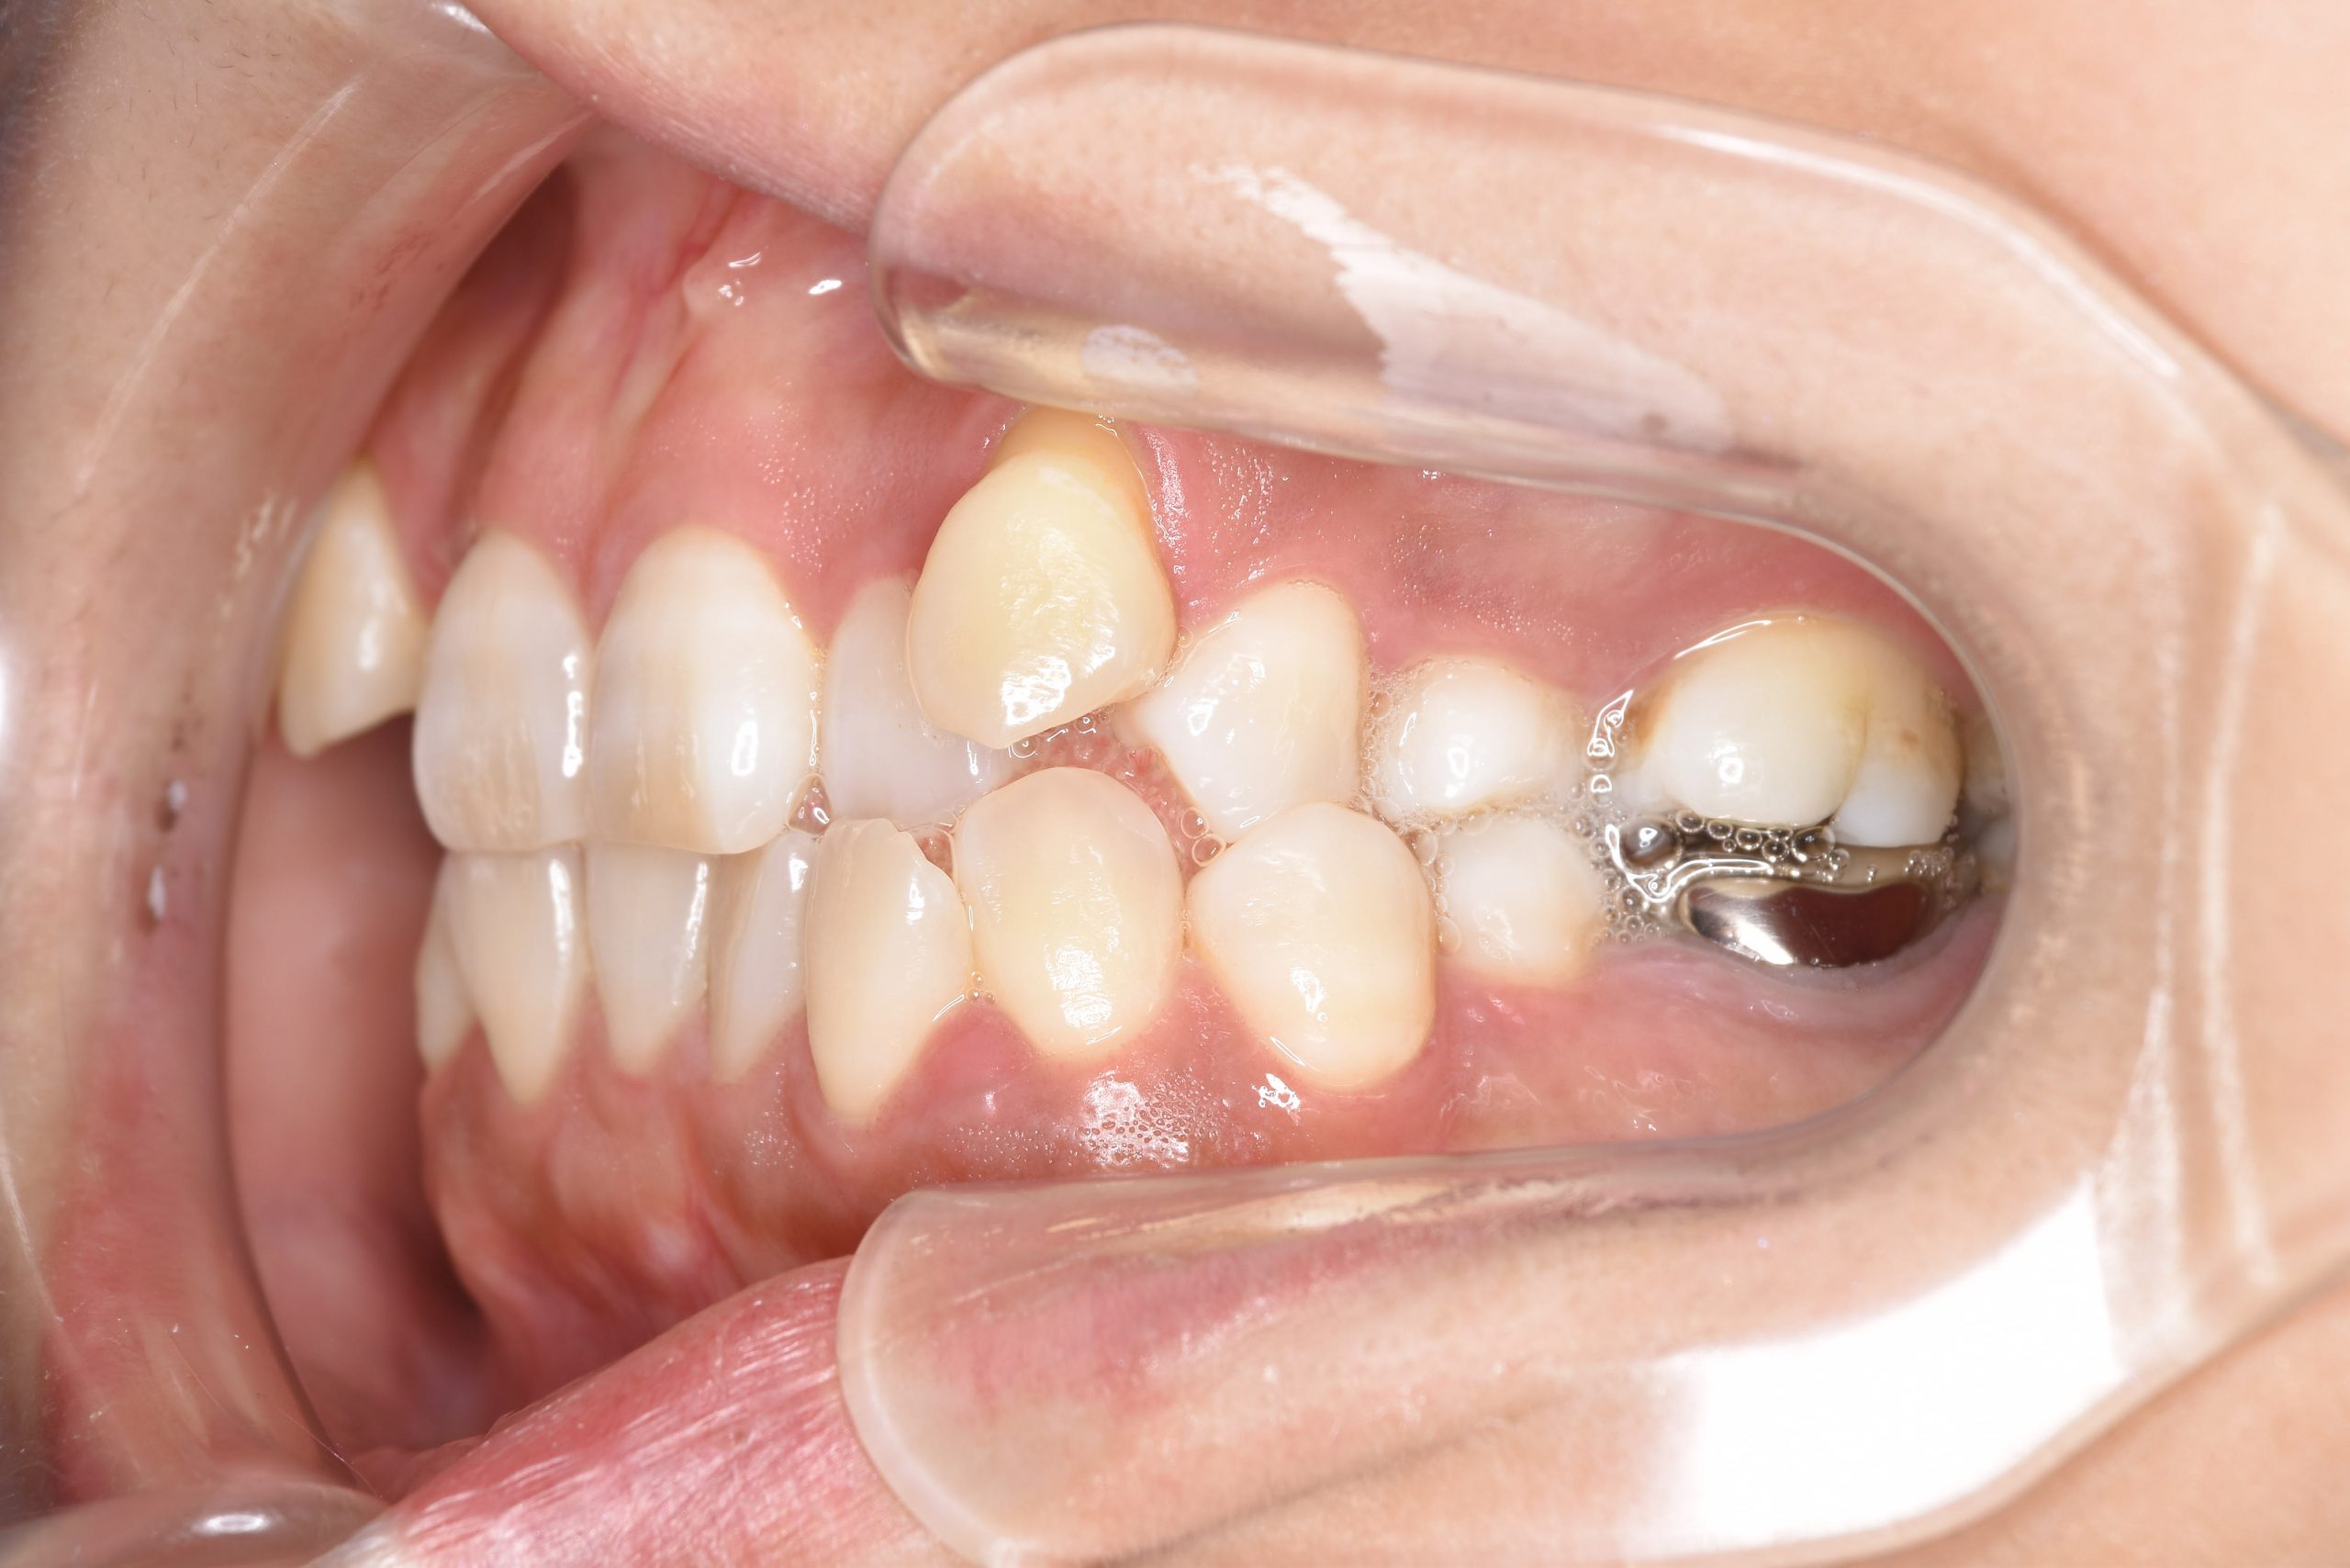

ビフォー

全顎ワイヤー矯正 症例_141

主訴 八重歯|上下センターがずれている

施術内容 成人矯正1期治療

治癒期間 4年10ヶ月間

費用 1,106,560円(税込)